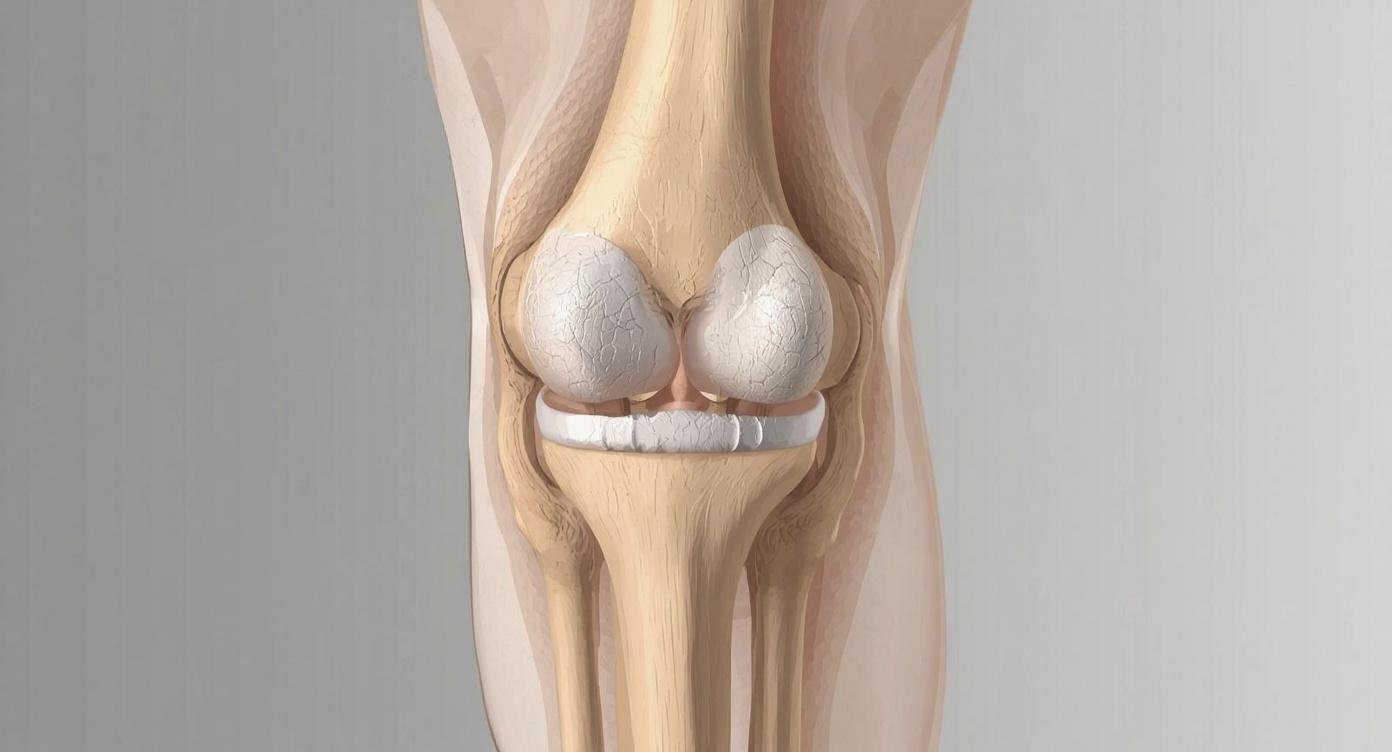

الفصال العظمي في الركبة هو حالة تنكسية مزمنة تحدث نتيجة تآكل الغضروف الذي يغطي أطراف العظام داخل مفصل الركبة. هذا الغضروف يعمل كوسادة تمتص الصدمات و تسمح بالحركة السلسة، ومع تآكله تبدأ العظام بالاحتكاك المباشر، مما يؤدي إلى الألم، التصلب، والالتهاب. نحن نلاحظ أن هذه الحالة تتطور تدريجيًا، وقد تستغرق سنوات قبل أن تصل إلى مراحل متقدمة.

ينقسم الفصال العظمي في الركبة إلى أربع درجات أساسية وفقاً لتصنيف كيلغرين لورانس، وهي:

الدرجة الأولى: خشونة طفيفة تظهر فيها نتوءات عظمية صغيرة جداً ولا يشعر المريض بألم مستمر.

الدرجة الثانية: خشونة بسيطة يبدأ فيها تآكل الغضروف بشكل جزئي مع ظهور آلام عند صعود الدرج أو المشي لفترات طويلة.

الدرجة الثالثة: خشونة متوسطة يحدث فيها ضيق واضح في المساحة المفصلية، وتزداد نوبات الالتهاب المتكررة وتيبس الركبة الصباحي.

الدرجة الرابعة: خشونة حادة أو متقدمة، حيث يتلاشى الغضروف تماماً ويحدث احتكاك مباشر بين العظام، مما يسبب تشوه شكل المفصل وصعوبة الحركة.